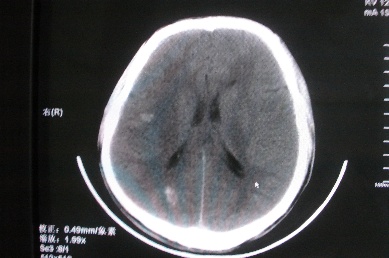

以下是引用zhangzhongshou在2007-4-18 17:49:00的发言:[br]脑实质内多发高密度结节影,支持肉芽肿得诊断,究竟是结核性、真菌性或寄生虫性的需结合临床,进一步检查确诊,但从影像上无法鉴别,只是临床上结核性肉芽肿最为多见而已。